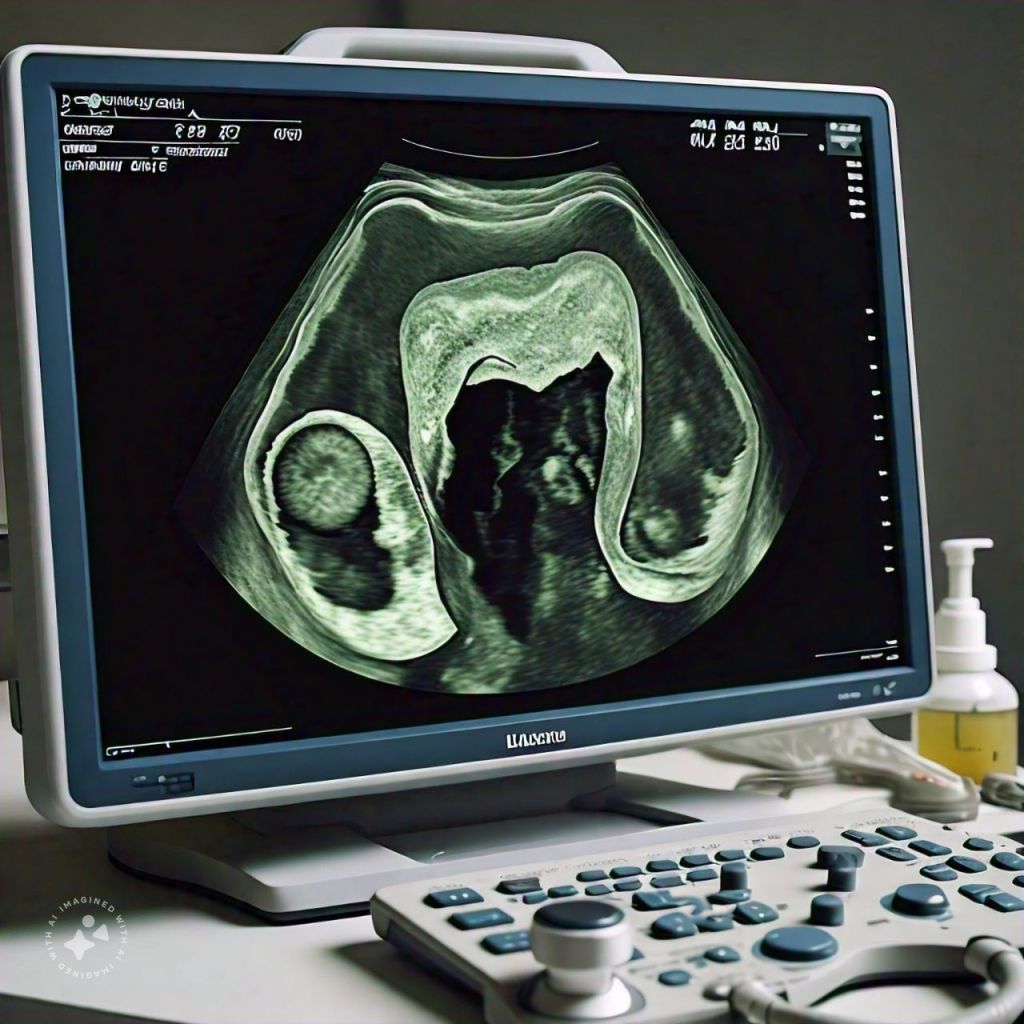

Uterine Fibroids is also known as leiomyomas. They are non-cancerous growths that develop in the uterus. They are common affecting up to 70% of women by age 50.

Fibroids known as uterine fibroids or leiomyomas are non-cancerous growths that develop in or on the uterus which is a part of the female reproductive system. Fibroids are quite common and many women may have them without experiencing any symptoms or issues.

These growths are made of muscle tissue and can vary in size, ranging from tiny almost undetectable nodules to large masses that can distort the shape of the uterus. The hormonal factors, particularly estrogen and progesterone seem to play a role in their development and growth.